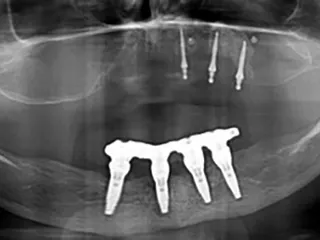

Seguida de la colocación inmediata de 4 implantes Straumann TLC™, ∅ 3,75 mm x 10 mm (44, 42, 32), ∅ 3,75 mm x 12 mm (34) SLActive®, Roxolid® y restauración provisional inmediata.